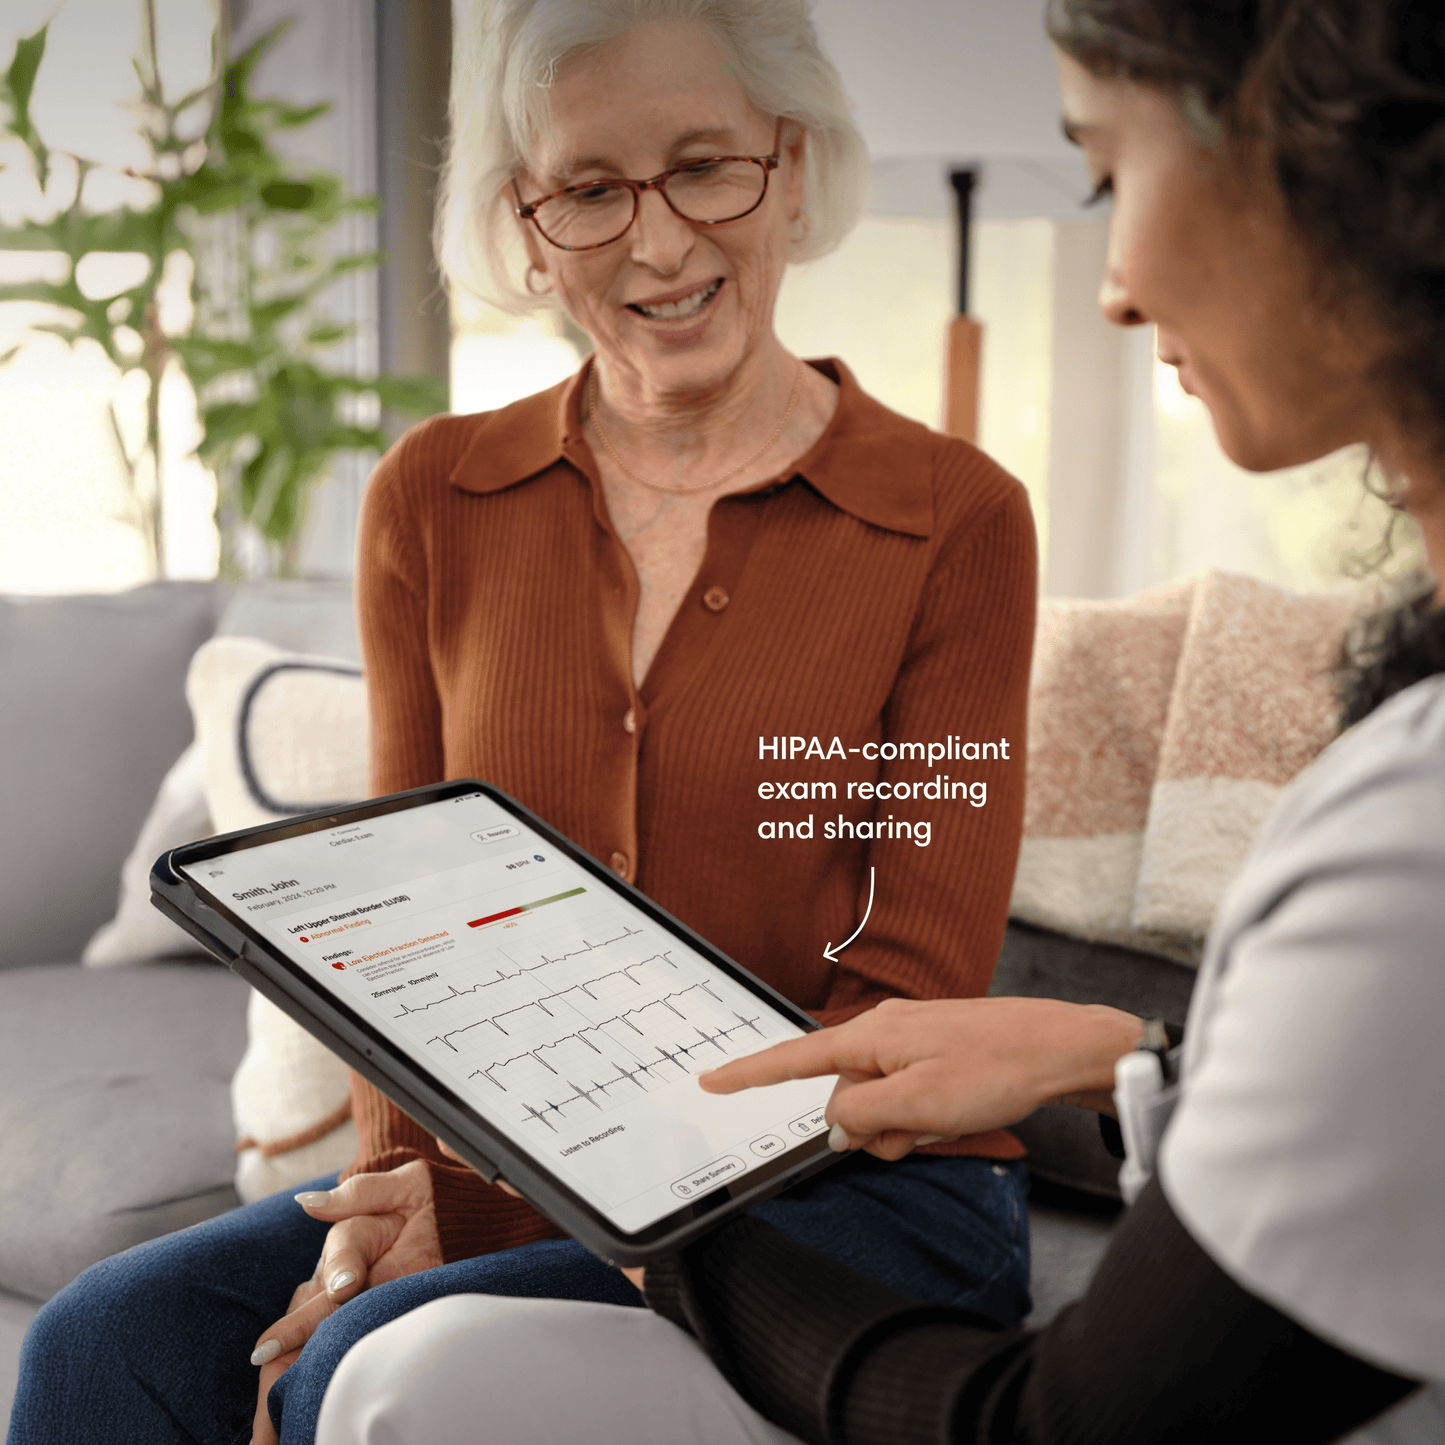

Save and share patient records.

Pair with the Eko App to save admin time, share data with colleagues, upload to your EMR, revisit past exam results, and monitor progress all while maintaining HIPAA compliance.